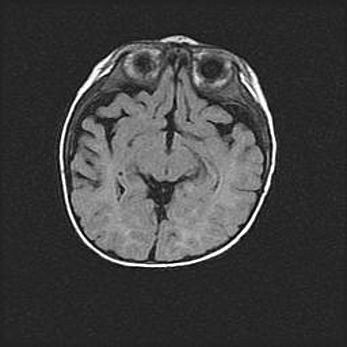

Лейкомаляция с кистозно-глиозной дегенерацией головного мозга.

Возраст: 2 месяца 25 дней

Вес: 6400 г

Окружность головы: 40 см

Срок гестации: 41 неделя

Лейкомаляцию относят к ишемически-гипоксическим повреждениям головного мозга, диагностируемым у новорожденных. При лейкомаляции в головном мозге обнаруживают очаги некроза, возникшие после тяжелой гипоксии и нарушения кровотока. В процессе морфогенеза очаги проходят три стадии: 1) развития некроза, 2) резорбции и 3) формирования глиозного рубца или кисты. Перивентрикулярная лейкомаляция (ПЛ) встречается примерно в 12% случаев среди новорожденных, обычно – у недоношенных детей, причем, частота ее зависит от массы, с которой младенец появился на свет. Наибольшее число малышей страдает лейкомаляцией, если масса при рождении 1500-2500 г.